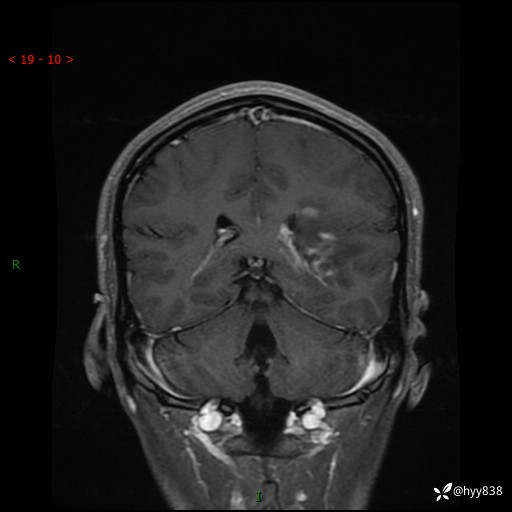

颅脑MRI平扫+增强